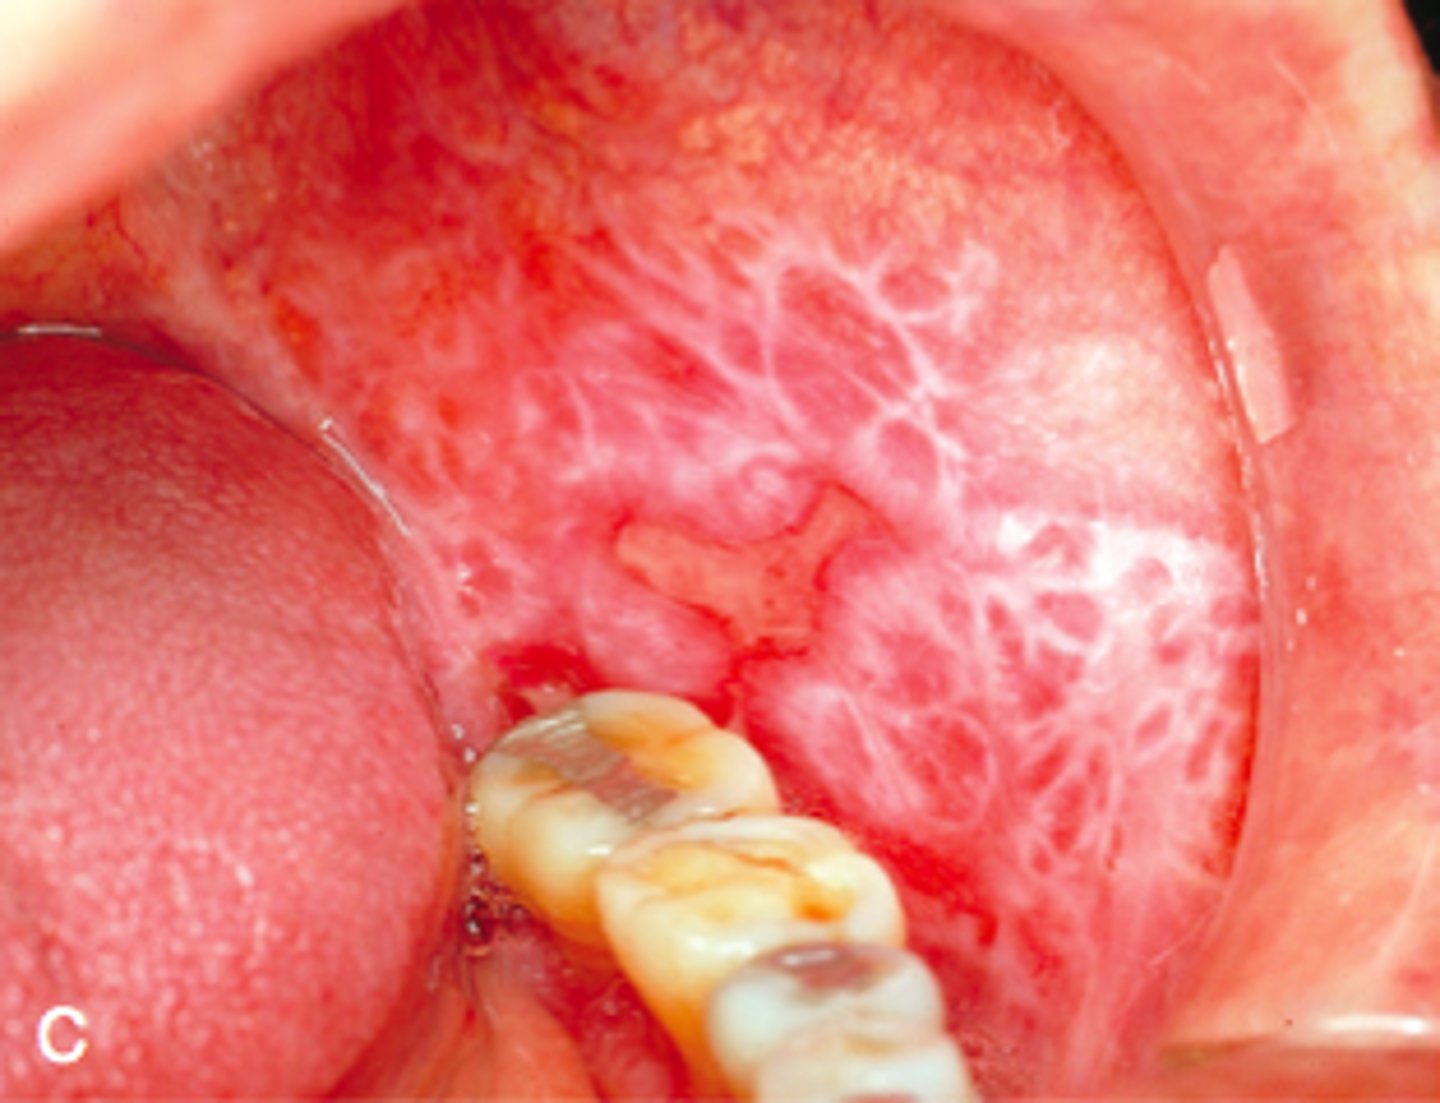

Tongue lesion is diagnosed as lichen planus. Lesion is asymptomatic, how do you treat?

- antifungal

- corticosteroids

- antibacterial

- chlorhexidine rinse

corticosteroids (there was no option for do nothing)

White lesion present on buccal mucosa. Likely diagnosis?

- leukoedema

- cheek biting

- lichen planus

- squamous cell carcinoma

lichen planus

- white lesion can be describe as Wickham striae